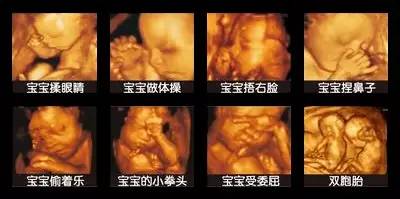

每个准妈妈都是兴奋和激动的,我家宝宝长什么样呢?是像他爸爸,还是像我呢?宝宝又动了,他在干什么呢?是自己玩呢,还是睡觉呢?是皱眉呢,还是笑呢?现在,四维彩超就可以给你一个准确的答案!这就是四维彩超带来的魅力,它能更清晰、更立体地把宝宝的一言一行,一举一动,生动地传达给孕妈妈,让孕妈妈和宝宝穿越时空提前相见

在这种情况下,四维彩超就展现了它强大的排查作用,四维彩超能够多方位、多角度地观察宫内胎儿的生长发育情况,能立体显示胎儿的颜色、面部轮廓及各器官的发育情况,甚至可以观察到胎儿在母体里的动作表情。为早期诊断胎儿先天性体表畸形和先天性心脏疾病提供准确的科学依据,最大限度的保障准妈妈生下健康的宝宝。

1.面部畸形:如唇腭裂、大小眼、鼻畸形、耳畸形等。

2.神经系统:无脑儿、脑积水、小头畸形、脊柱裂及脑脊膜膨出。

3.泌尿系统:肾积水、多囊肾及巨膀胱、尿道梗阻等。

4.消化系统:脐部肠膨出、内脏翻出、肠道闭锁及巨结肠等。

5.其它畸形筛查:脊柱畸形、腹部畸形、短肢畸形、联体畸形、先天性心脏病及畸胎病等。